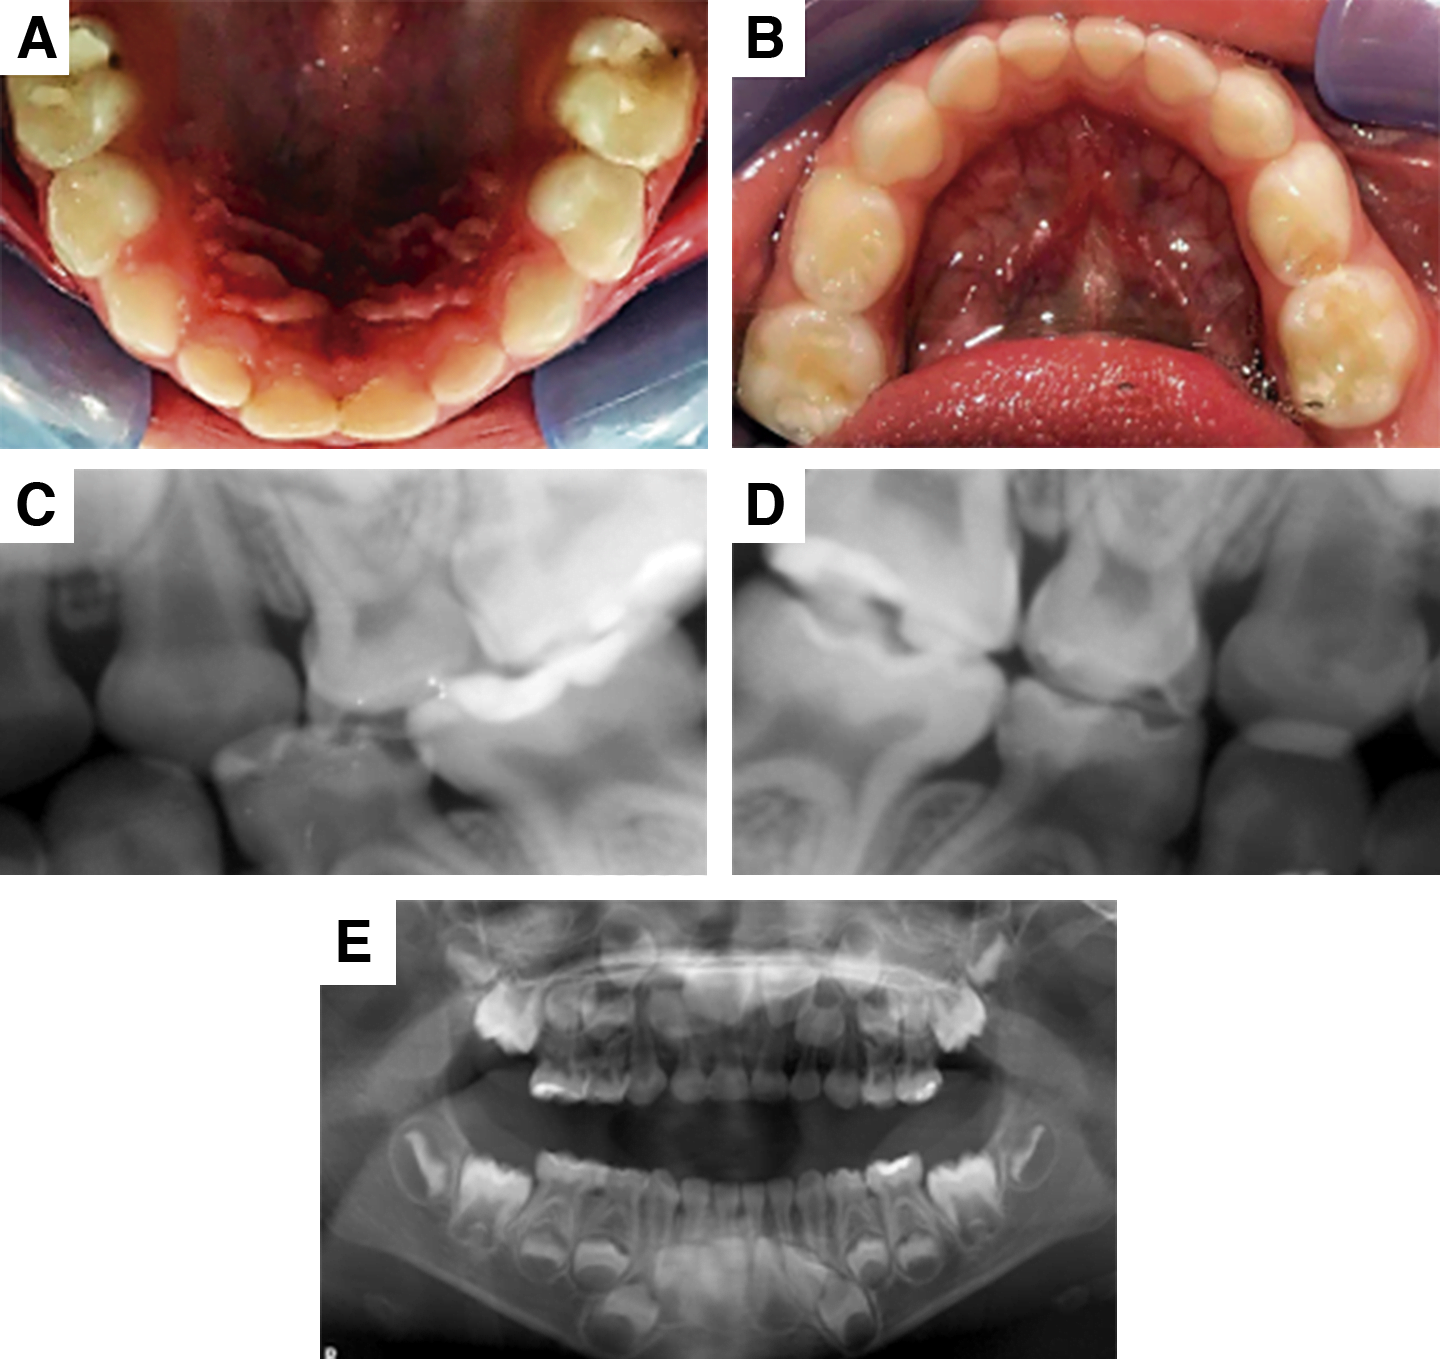

A la anamnesis se encuentra que el paciente no presenta ante- cedentes heredofamiliares con diagnóstico de atresia pulmonar. A la exploración intrabucal se encontraron mucosas cianóticas y la presencia de lesiones cariosas y restauraciones previas filtradas (figura 1A y B). No refiere molestias en cavidad oral. A pesar de ello, se observa a un paciente poco colaborador, ya que había tenido experiencias previas negativas en el sillón dental. Para poder hacer el tratamiento de manera eficaz, se estableció un adecuado manejo de conducta durante la consulta dental. Mantener al paciente libre de estrés e incertidumbre durante las citas fue la piedra angular que permitió manejar el caso de manera exitosa.

El tratamiento odontológico inicial consistió en la toma de radiografías de aleta de mordida de los cuatro cuadrantes (figura 1C y D), además de una radiografía panorámica (figura 1E). Se realizó interconsulta con el cardiólogo pediatra explicando el diagnóstico obtenido de la revisión clínica intraoral y examen radiográfico, con el fin de discutir el uso de medicamentos anticoagulantes que se estaban utilizando, lo que podría ocasionar problemas relacionados con la hemostasia. Se discutieron los riesgos del paciente de presentar EI, así como la manera de prevenirla.